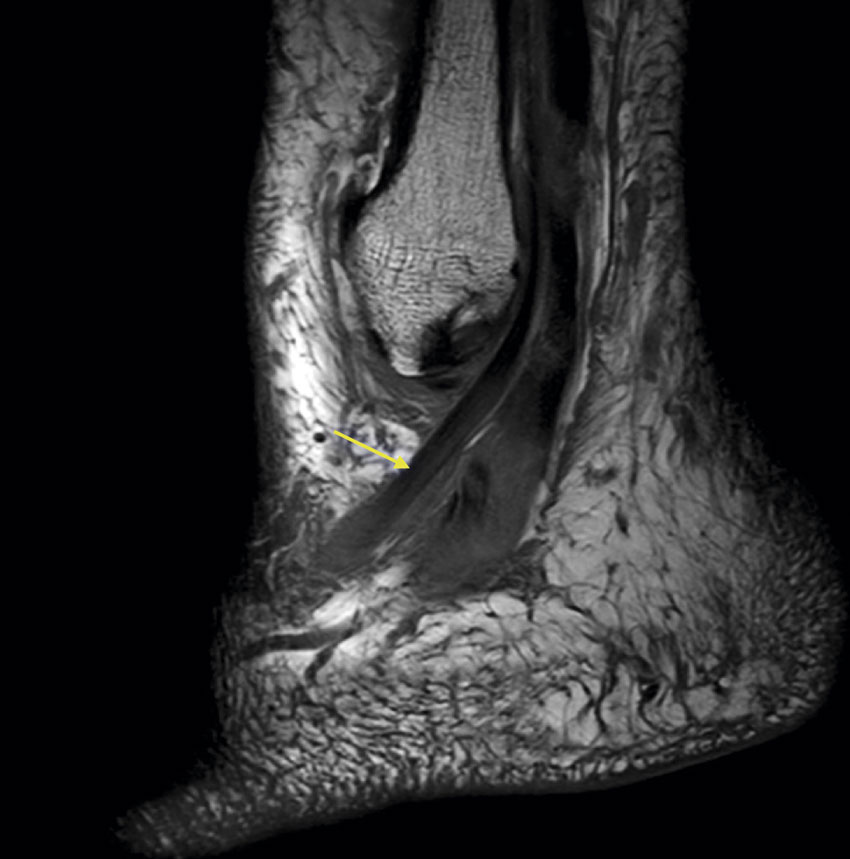

Medicinens ABC Plantarfasciopati, akillestendinopati och peroneusseneruptur